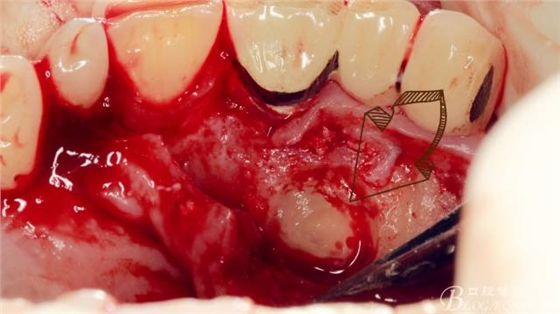

長柄裂鉆分離牙冠,微創(chuàng)挺插入后順時針或者逆時針輕擰一下,手上去感受牙冠斷開的那一瞬間,有時候耳朵也能聽見啪得一聲,不過此刻因為牙冠周圍的骨阻力,牙冠是不能取出的。

T形分牙,把牙冠分為兩瓣,減少阻力。

分別挺出兩瓣牙冠,可見牙根截斷面。